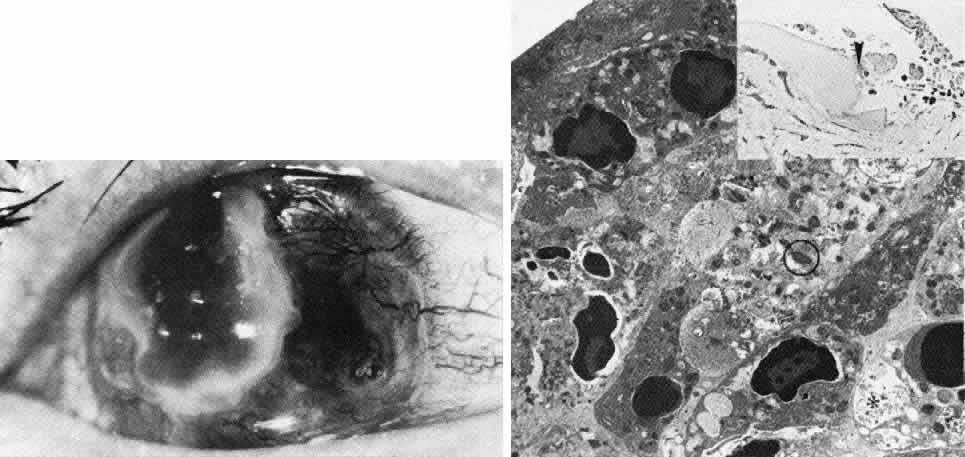

Sclerocornea

In sclerocornea (Fig. 4), the limbus is ill-defined since opaque scleral tissue with fine vascular conjunctival arcades extends into the peripheral cornea. A broad range of corneal involvement is possible, with the most extreme being complete sclerification of the cornea. Ninety percent of cases are bilateral, although generally asymmetric. Most cases are sporadic; there is no known heredity. Sclerocornea is nonprogressive and must be differentiated from interstitial inflammatory conditions and arcus juvenilis (congenital peripheral lipid deposition, also known as anterior embryotoxon). Sclerocornea is associated with cornea plana in approximately 80% of cases.44 Other associated ocular abnormalities include microphthalmos, iridocorneal synechiae, persistent pupillary membrane, dysgenesis of angle and iris, congenital glaucoma, colobomas, and posterior embryotoxon of the fellow eye.45 Somatic abnormalities sometimes occur along with associated chromosomal abnormalities; they include mental retardation, deafness, and craniofacial, digital and skin abnormalities.44

Fig. 4. Sclerocornea. Schematic drawing of ocular features Top left. In a minimally affected patient with additional findings of ptosis, strabismus, and hearing loss, only the peripheral cornea is opacified. Top center. In this advanced case with chromosomal translocation and multiple congenital abnormalities, the entire cornea is sclerified and the fine vascular arcades extend centrally from the conjunctiva and sclera. Top right. Light micrograph of anterior cornea shows edematous disorganization of epithelium, fragmentation of Bowman's membrane (B), and interstitial vascularization (V) (hematoxylin-eosin, × 200). Middle left. Transmission electron micrograph of normal human corneal stroma is shown for comparative purposes. Note uniform 240- to 260-nm collagen fibril diameter (× 50,000). Middle right. Transmission electron micrograph of sclerocornea at same magnification shows disorganized array of collagen fibrils that measure as much as three times normal diameter (× 50,000). Bottom. Transmission electron micrograph of posterior cornea shows abnormal Descemet's membrane of less than 1μm thickness (DM, bracketed) and attenuated endothelial cells (× 10,500). (Schematic. Grayson M: Diseases of the Cornea, p 32. St. Louis, CV Mosby, 1979; Top center and right. Rodrigues MM, Calhoun J, Weinreb S: Sclerocornea with an unbalanced translocation [17p, 10q]. Am J Ophthalmol 78:49, 1974)

Ultrastructural studies22,46,47 have shown the involved stroma to assume the morphologic features of scleral tissue, with irregularly arranged collagen fibrils of variable and immensely enlarged diameter for corneal tissue (up to 150 nm, comparable to normal scleral collagen). The precise lamellar organization of normal corneal stroma is not present; thus optical clarity is not achieved. Various abnormalities of endothelium and Descemet's membrane exist, from attenuation to focal absence. Descemet's membrane is generally thin, with multilaminar deposition of basement membrane-like collagen.

Pathophysiologically, sclerocornea may result from developmental arrest of limbal differentiation during neural crest migration, as occurs with the other mesenchymal dysgeneses.22